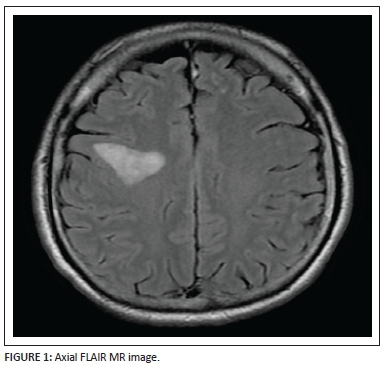

An axial FLAIR (Figure 1) sequence reveals a triangular focus of hyperintensity at the right subrolandic frontal white matter in the centrum semiovale. This lesion, for its size, is not associated with any significant mass effect and there is no disruption of the grey-white matter interface. Incidentally, a few left frontal subcortical hyperintensities are also observed, probably microangiopathic in origin.